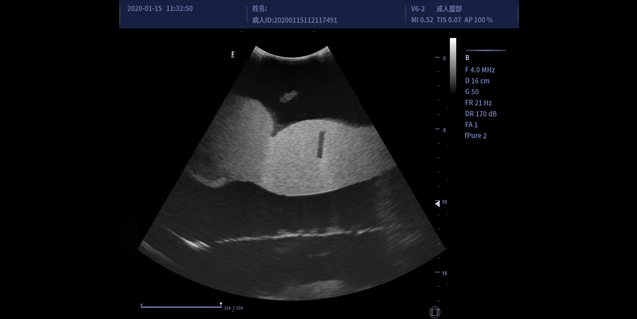

适用于腹部,妇产,泌尿等